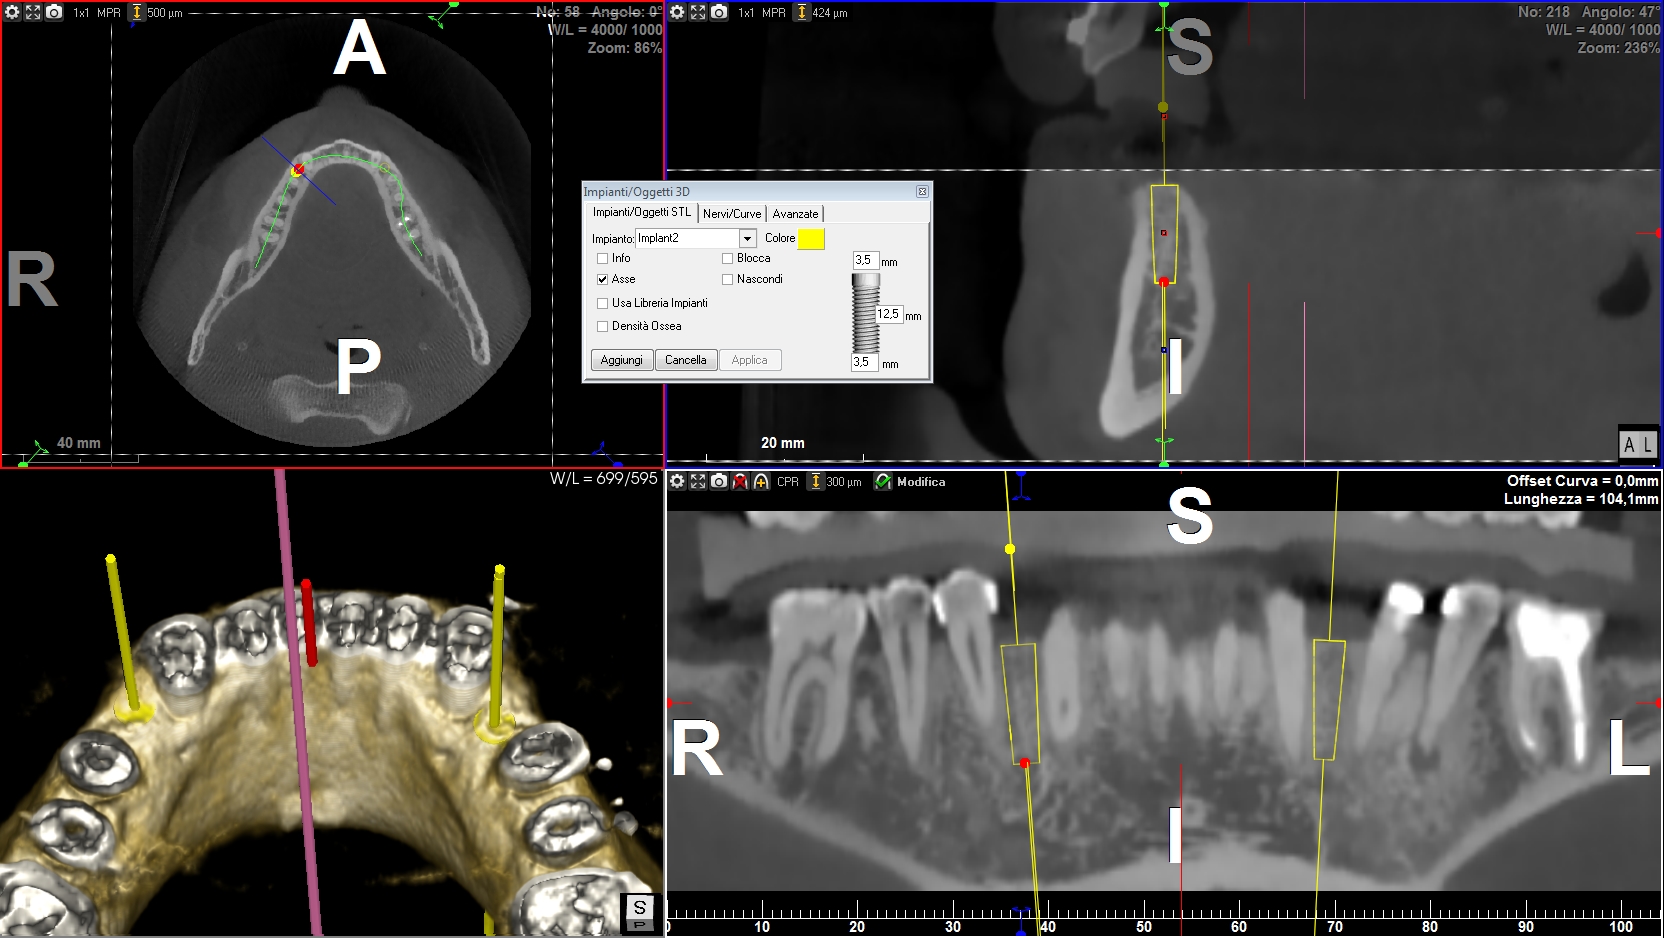

Progettazione virtuale / chirurgia guidata Un esempio della progettazione 3D di un intervento di posizionamento implantare SENZA BISTURI. Photogallery: